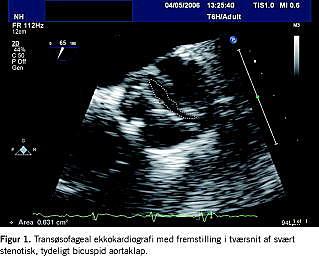

Omkring 50% af alle voksne med svær aortastenose har BAK [14]. Aortaklappen er typisk svært kalcificeret, men har bevaret sin bicuspide afgrænsning (Figur 1 ) i modsætning til aortastenose ved tricuspid klap, hvor stenosen udvisker klappens oprindelige morfologi [4]. Sklerosering af den bicuspide klap begynder almindeligvis i anden dekade og gør patienten symptomatisk i 5.-6. dekade. Patienter med BAK har behov for aortaklapoperation gennemsnitlig fem år før tilsvarende patienter med tricuspid aortaklap [15]. Højt serumkolesterol og rygning er uafhængige risikofaktorer for udvikling af aortastenose og formodes at medvirke til aldersdegeneration af klappen [16, 17].